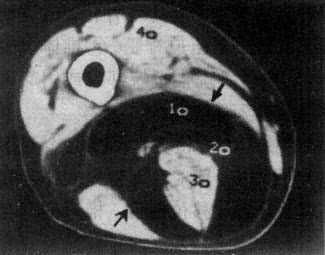

软组织肿瘤的密度一般低于正常肌肉,增强扫描可增加病变和正常肌肉的密度差,多数良性肿瘤边界清楚或有包膜且质地均匀,但定性诊断有一定限度。脂肪瘤因有典型的脂肪密度,表现具有特征性(图2-2-1)。海绵状血管瘤于肿块内可见小圆形静脉石,且在造影增强扫描后,肿瘤明显强化,具有一定的特点。

图2-2-1 大腿脂肪瘤

右大腿中1/3后内侧低密度肿块,境界清楚,CT值-100Hu